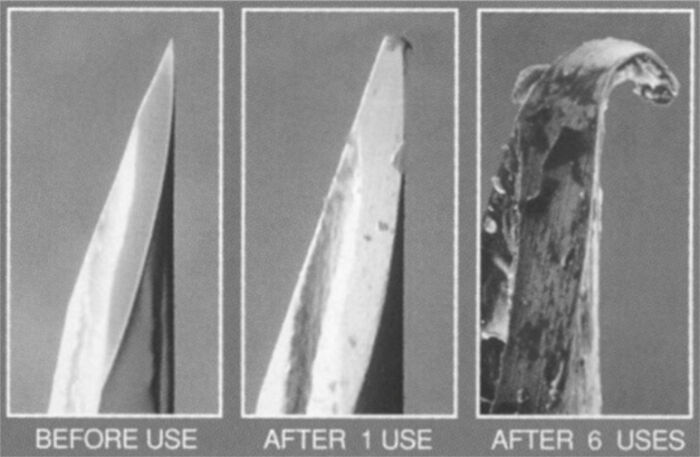

Head Of A Needle Under A Microscope